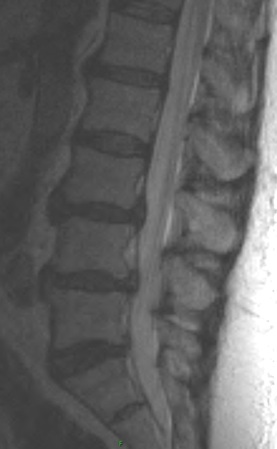

1. Aside from disc changes and spondylosis, what additional finding is present.

2. What are the types of spondylolisthesis? Pertaining to the anterolisthesis, which type does the patient have?